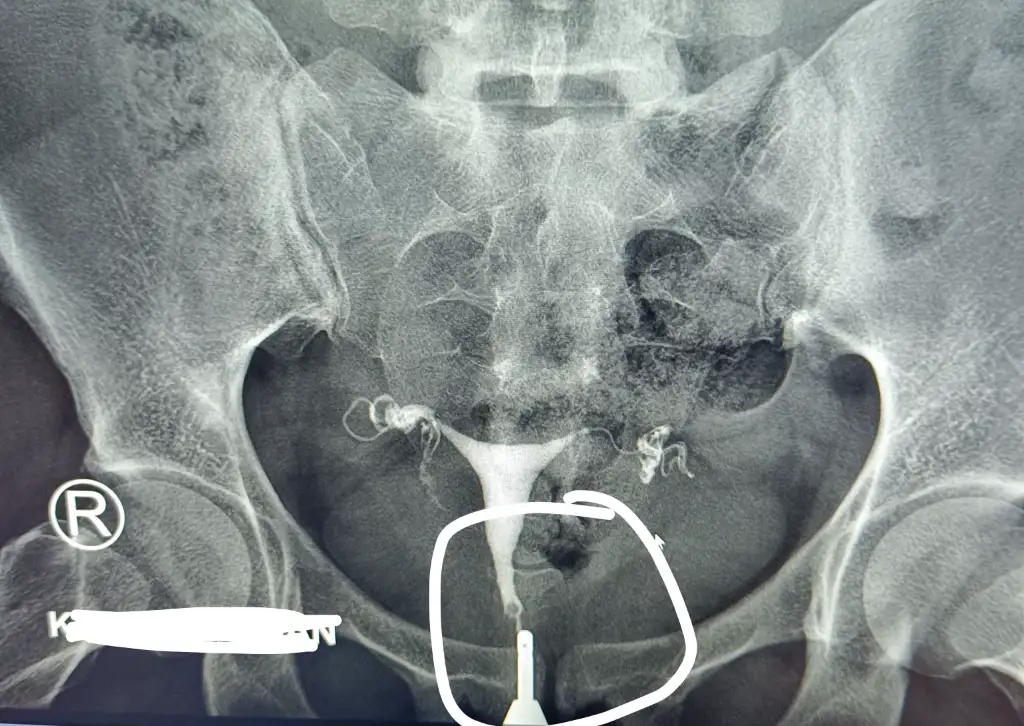

HİSTEROSALPİNGOGRAFİ TETKİKİNDE:

- Uterus orta hatta izlenmektedir.

- Uterus kavitesi “Y shape” (Y şeklinde) izlenmiştir.

- Her iki tubanın (fallop tüpleri) interstisyel, isthmik ve ampuller segmentleri normaldir.

- Skopik gözlem sırasında ve elde olunan grafilerde kontrast madde her iki tubadan peritona geçmiş ve periton içinde serbest olarak dağılmıştır.

SONUÇ: Histeroskopi önerildi.

- Görüntüde rahim boşluğu orta hatta ve belirgin bir Y şekli çiziyor.

- Tüpler açık, kontrast maddeler dışarıya rahatça geçmiş.

- Bu nedenle tüplerle ilgili bir problem yok.

- Görüntü, septat uterus şüphesini düşündürür ancak bu tanı için HSG yeterli değildir